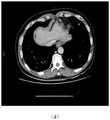

图8是本发明实施例提供的第二阶段肝占位识别模型对不同复杂病灶的分割结果示意图。FIG. 8 is a schematic diagram of a segmentation result of different complex lesions by a second-stage liver occupancy recognition model provided by an embodiment of the present invention.

图中:(a)微小型病灶分割实例;(b)边缘型病灶分割实例;(c)异质型病灶分割实例;(d)弥漫型病灶分割实例。In the figure: (a) Segmentation example of tiny lesions; (b) Segmentation example of marginal lesions; (c) Segmentation example of heterogeneous lesions; (d) Segmentation example of diffuse lesions.

实施例二,模型第二阶段对于肝脏图像中肝占位的识别。随机挑选模型在不同肝脏病变下对肝占位的分割结果,如图8所示,模型能够很好的处理识别难度大、隐秘性强的各类情形,主要包含:图8(a)微小型病灶;图8(b)边缘型病灶;图8(c)异质型病灶;图8(d)弥漫型病灶。Embodiment 2: The second stage of the model is for the identification of liver occupancy in liver images. Figure 8 shows the segmentation results of the liver occupancy by the randomly selected model under different liver lesions. The model can well handle various situations with high identification difficulty and strong concealment, mainly including: Figure 8(a) Miniature Lesions; Figure 8(b) Marginal lesions; Figure 8(c) Heterogeneous lesions; Figure 8(d) Diffuse lesions.